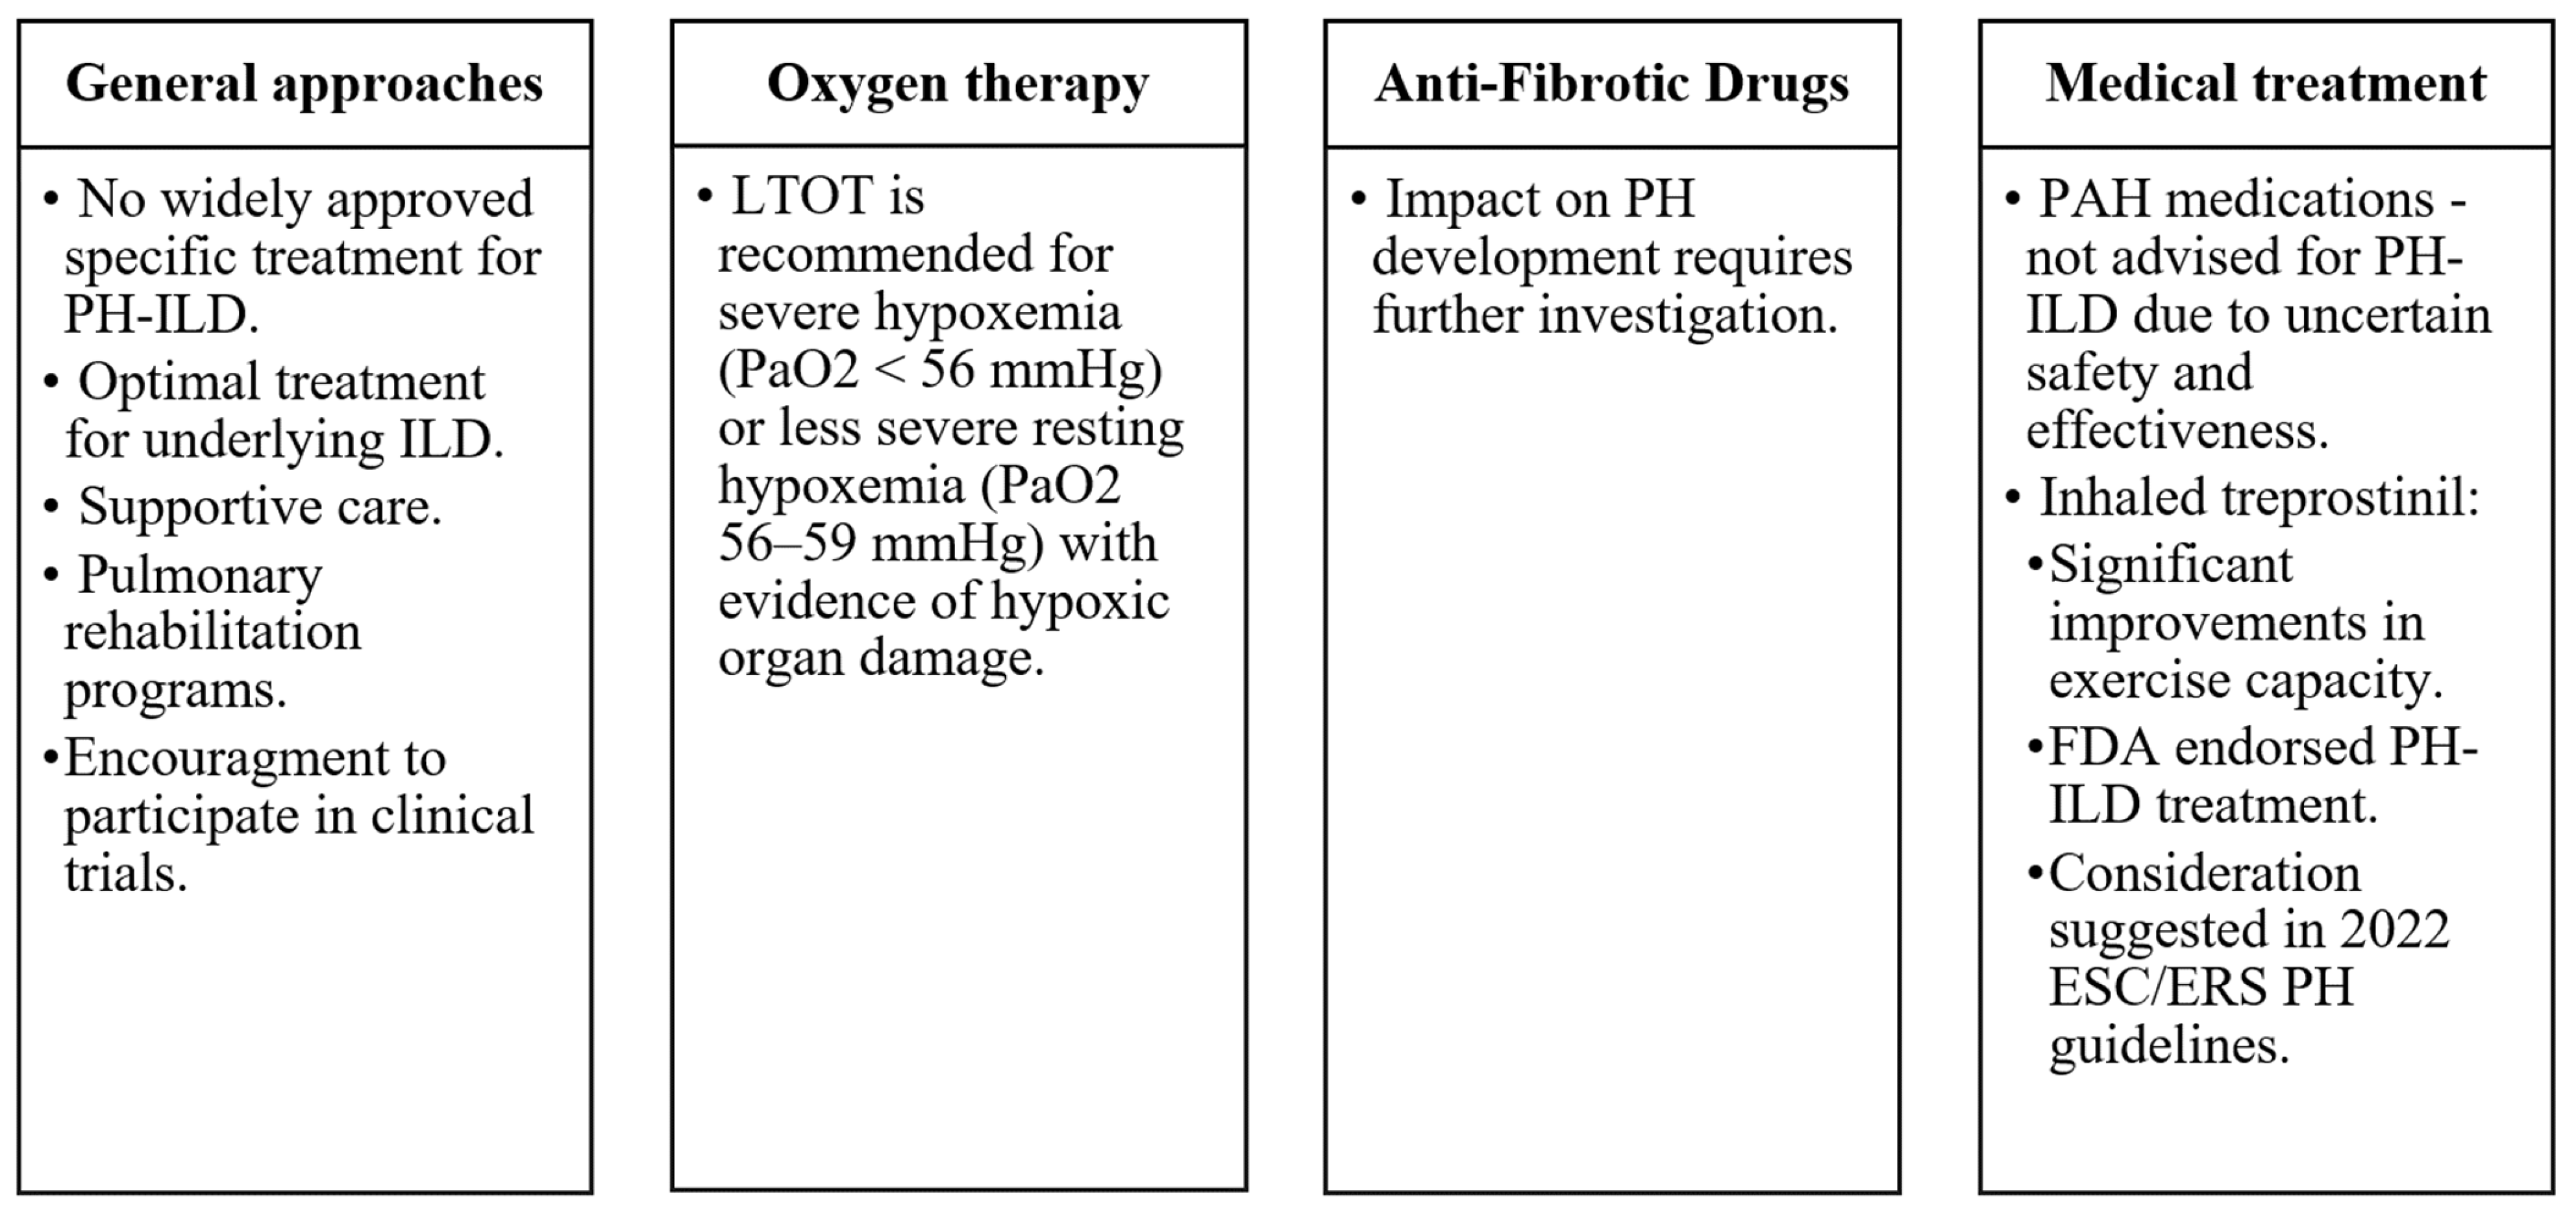

8. Management and Treatment

- There are currently limited specific treatments for PH-ILD, but recent trials with inhaled treprostinil show promise.

- -

- Managing PH-ILD involves supportive care, long-term oxygen therapy, and, in some cases, lung transplantation, with a focus on improving patient quality of life and prognosis.